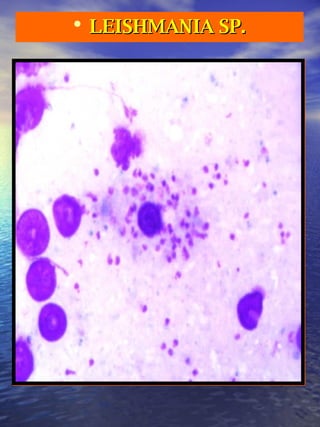

This document lists different life stages and species of two parasitic protozoa: Leishmania and Plasmodium. It describes the amastigote, promastigote and epimastigote forms of Leishmania and the trophozoite, gametocyte and schizont stages of several Plasmodium species which cause malaria, including P. falciparum, P. ovale, P. malariae, P. vivax, and P. cruzi.